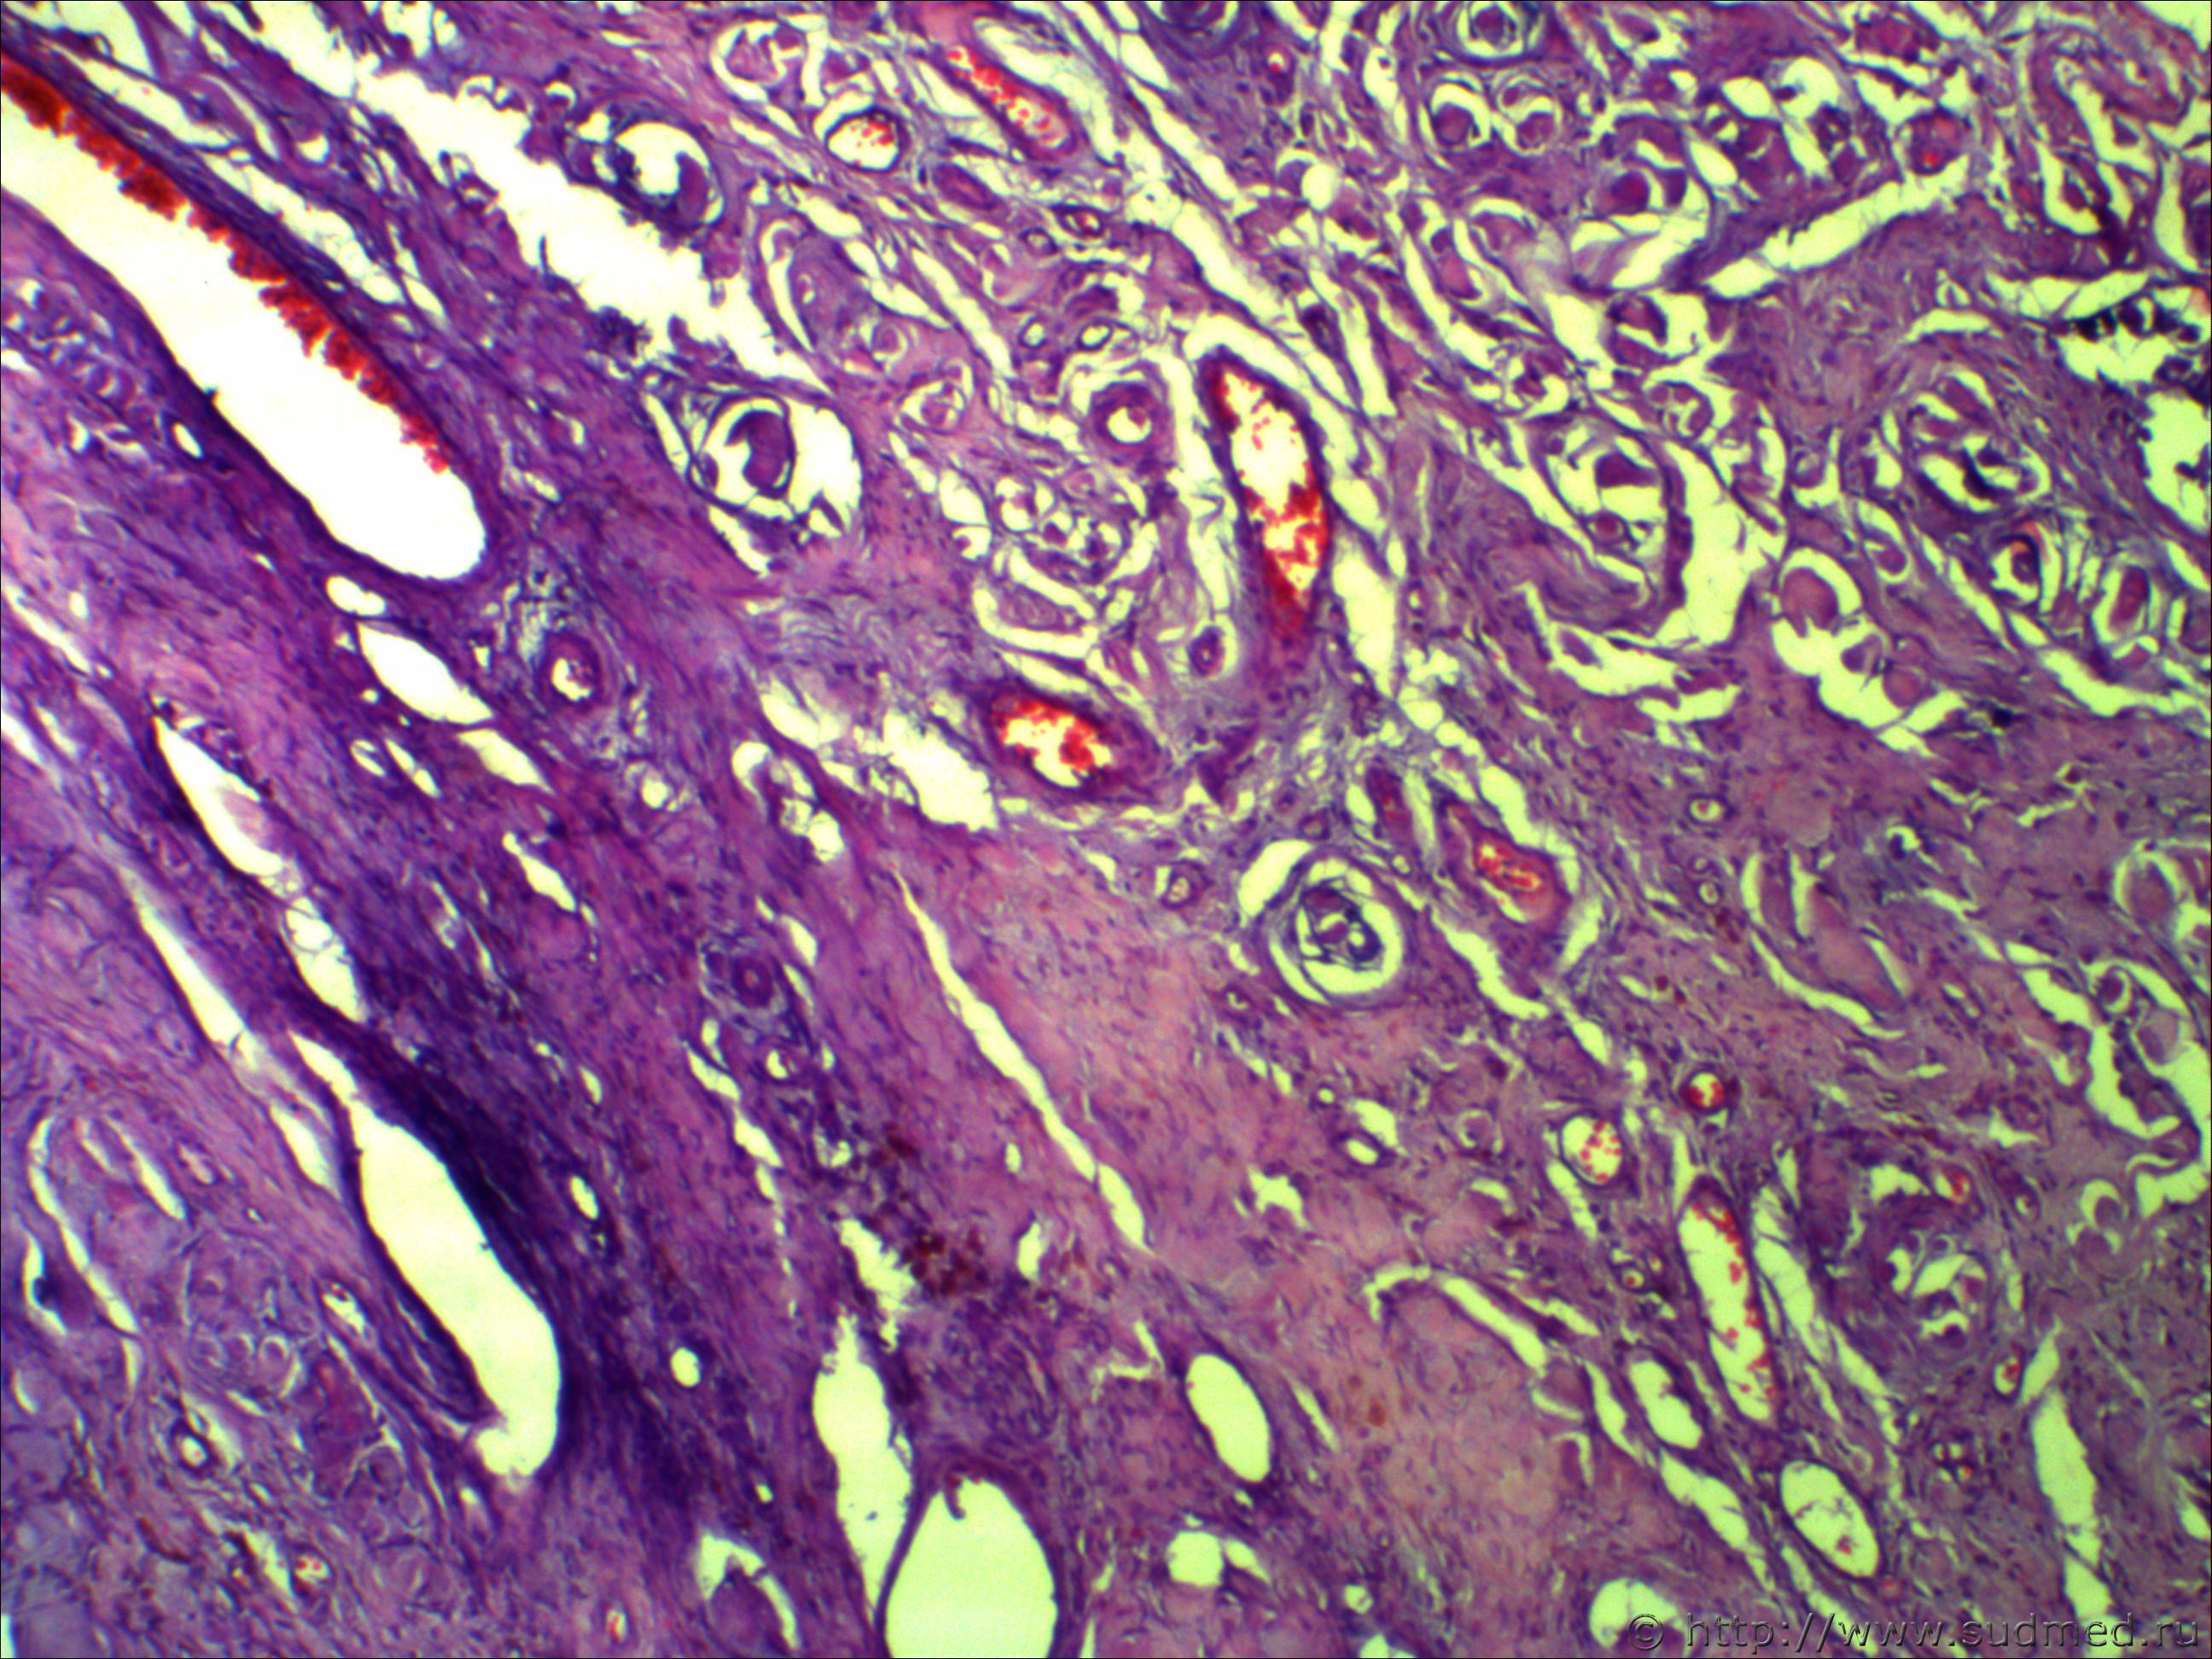

Н/О округлой формы четких границ, на теле фибринозно-кистозной структуру 5*7см!

Похоже на ангиофиброму.

Не фибринозно, а фиброзно-кистозная структура. Пока об ангиофиброматозе нужно думать, требует дальнейшей дифференциации.Срезы толстые. Наблюдается эндотелиальная пролиферация...

Ничего такого не понял, вижу:

- новообразование сосудов. полнокровие очаговое

- очаговый гиалиноз

- смешанную фиброму (типическую)... да их столько с примесью кистозного элемента

- митозов не вижу